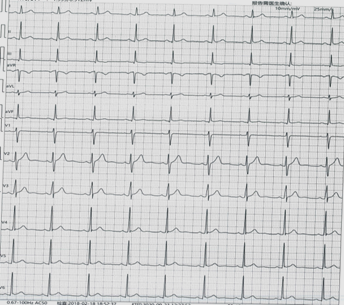

此心电图诊断为

A.窦性心动过缓

B.大致正常心电图

C.三度房室传导阻滞

D.心房颤动

『正确答案』B